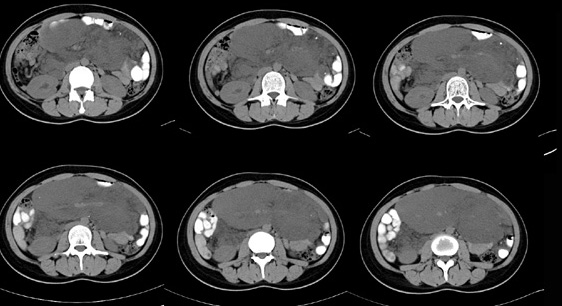

女性,28岁,停经3月,腹部膨隆1月,产前检查发现腹部占位

{肿块中心ct值27hu,增强后,动脉期、门脉期均无明显强化)

患者手术病理:腹腔囊性淋巴管瘤,象这样充满整个腹腔的的确很少见